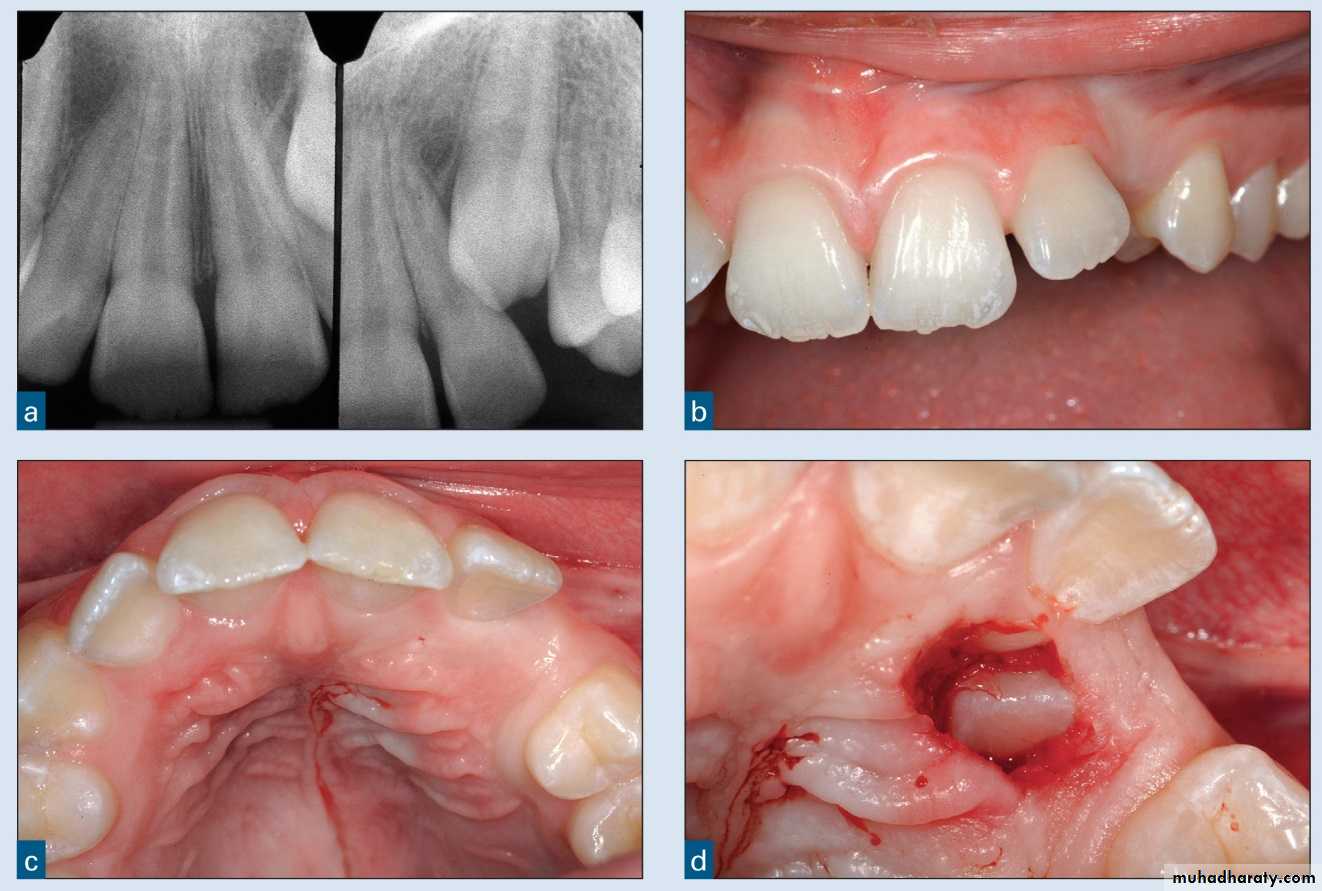

Interceptive orthodonticsThe phase of the science and art of orthodontics employed to recognize and eliminate potential irregularities and malpositions in the developing dentofacial complex.

Interceptive orthodontic

Serial extraction

Eliminate initial crowding and cross bit

Eliminate bad habit

Remove frenum attachment

Remove pathologic condition ( cyst , lesion , granuloma …....)

Remove supernumerary teeth